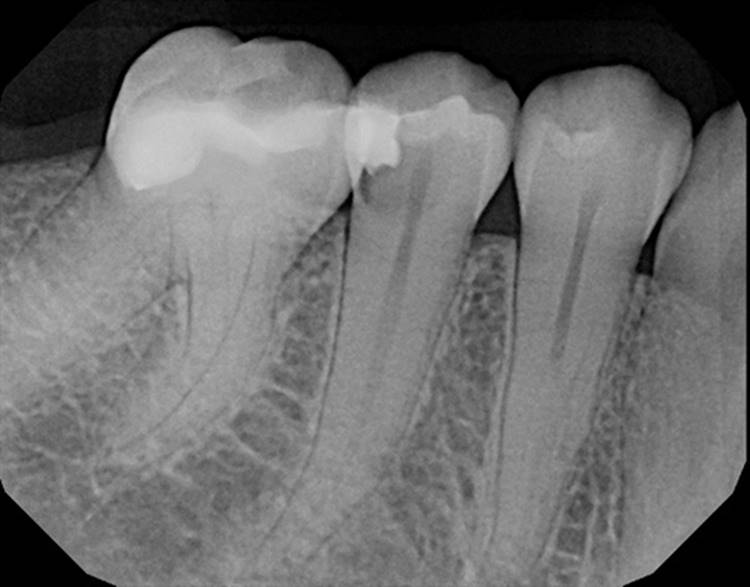

Forgive the sensor change from the first two cases to the last two. The good sensor broke and the back up isn’t as great.

EdgeFile® Cases